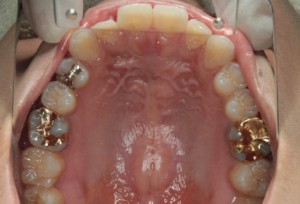

作成前

新規作成後の調整中